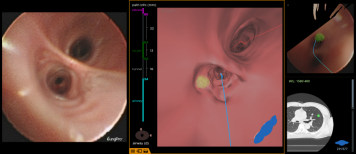

原来,陈恩国主任医师团队运用了最新的BTPNA技术,简单来讲,就是在原有的导航技术上升级了一个经支气管向病灶方向打隧道的办法。 这样,很多原来没有支气管相联通的肺结节,常规导航技术难以到达,现在也可以通过这个技术轻易到达啦! 虽说就是打一条通往结节的隧道,但其中技术含量可没那么简单。要保证安全和准确,术前精密的计算和路径设计非常重要。 王大伯术前,陈主任呼吸内镜介入团队利用最新一代的虚拟导航Lung pro系统对王大伯的胸部CT进行了三维重建,计算出最佳经支气管镜到达病灶的路径,并对手术路径的可行性进行讨论,对可能出现的各种情况进行分析。

术前规划/评估:病灶位置及最佳气道内路径

术中情况

尽管结节比一颗花生大不了多少,但凭借团队医生高超的技术,以及呼吸内镜中心导航系统及DSA的加持,穿刺针穿过管壁,顺利找到了病灶,为了多维度保证位置的准确,介入团队此次利用高大上的锥形束CT进行术中实时定位,确保万无一失。

CBCT确认活检钳位置准确无误,术者开始活检,取材满意。术中快速现场细胞学评估提示腺癌。